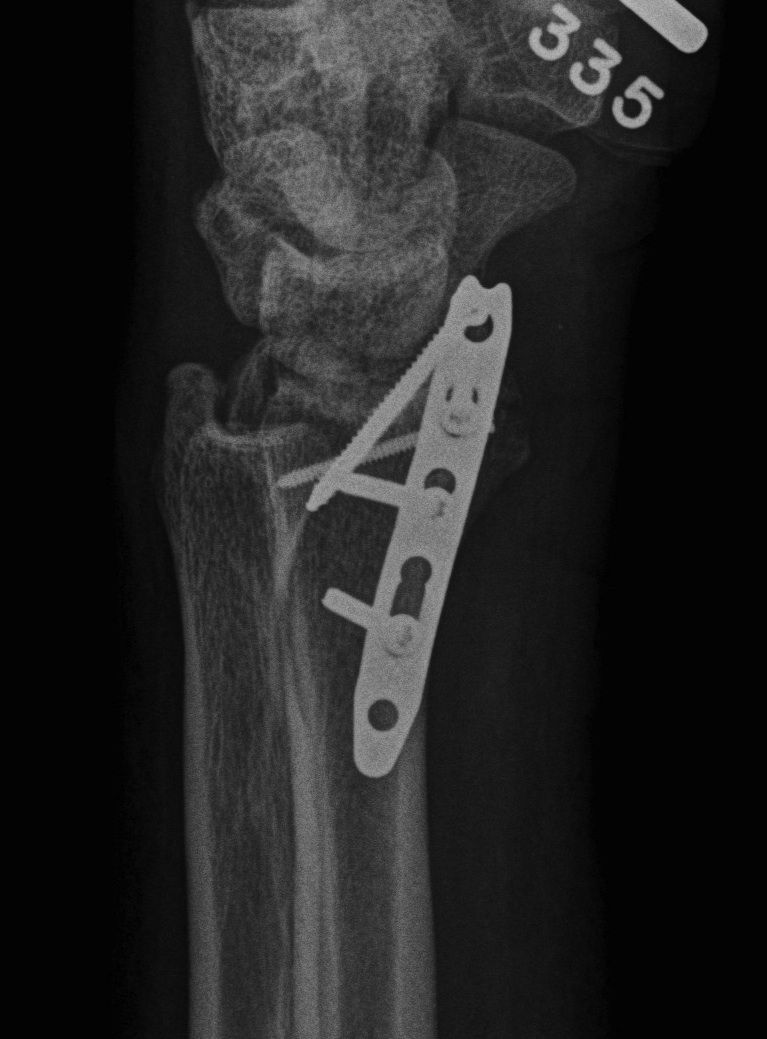

Radial styloid + dorsal rim fractures

Bridge plate

- distal to index / middle metacarpal

- slide under 2nd extensor compartment (ECRL / ECRB)

- proximal to radius between brachioradialis and ECRL / ECRB

- leave for 10 - 12 weeks

Radial styloid

- percutaneus screws +/- radial styloid plate